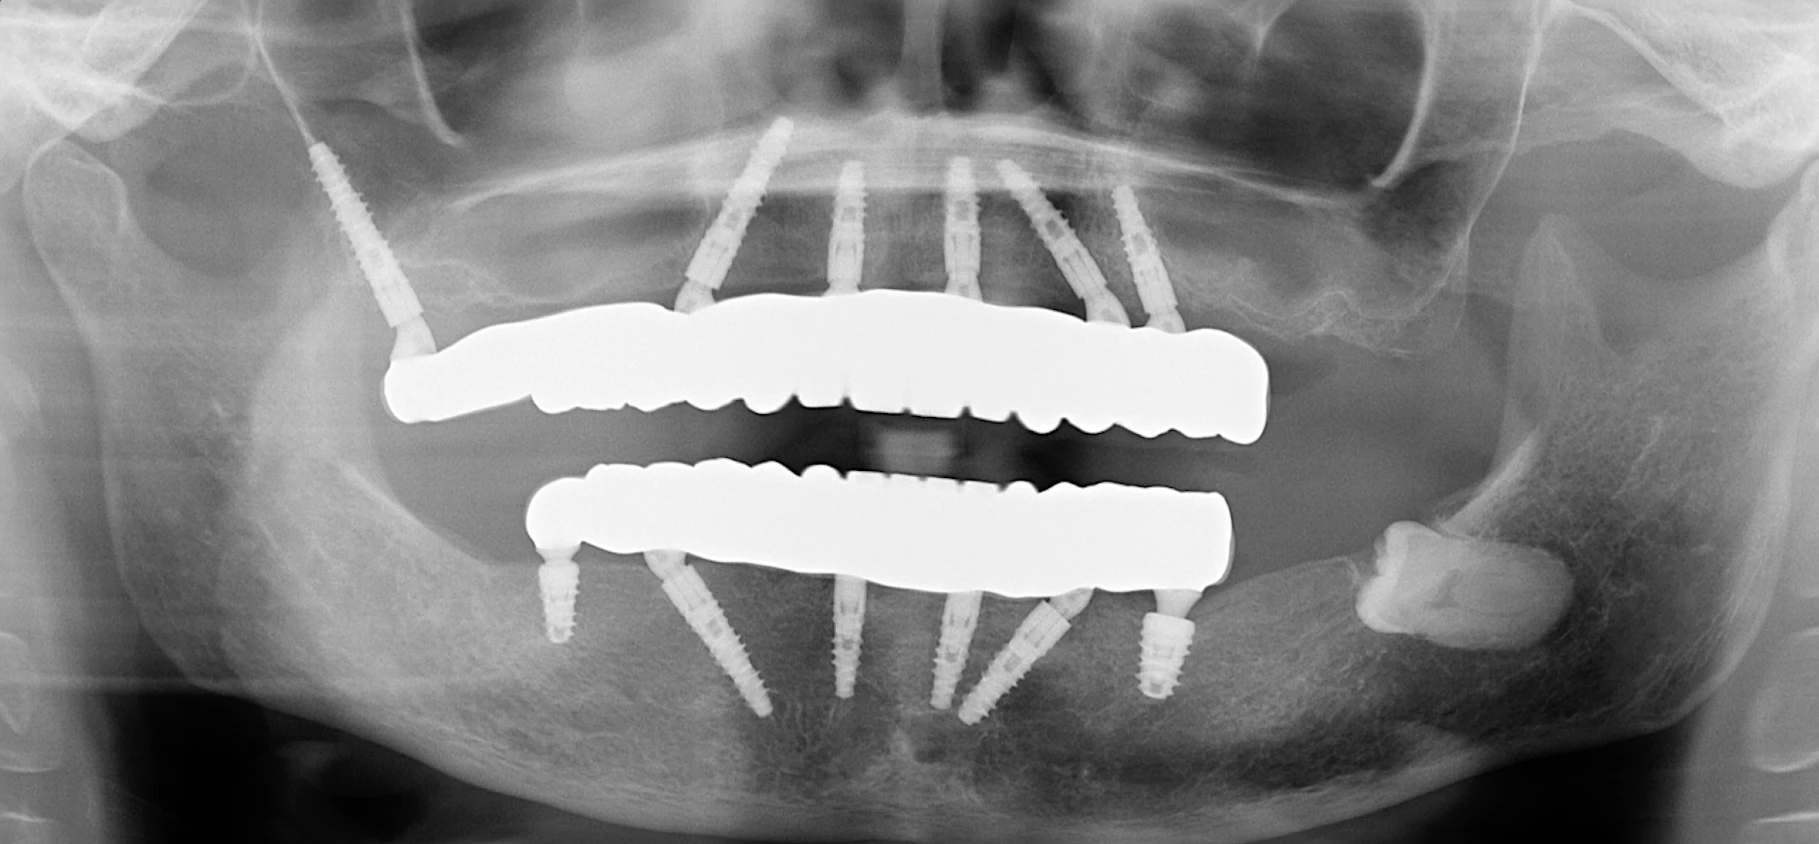

A panoramic x-ray showing a patient after all on 6 dental implants.

By using a combination of standard and longer implants, our team could engage the densest parts of her jawbone. This technique, known as bicortical stabilization, provides the immense primary stability needed to attach a full set of teeth on the same day as the surgery. This same-day approach is a key part of the process, as it means patients can avoid the discomfort of a removable denture and leave the office with a fixed, functional smile immediately.